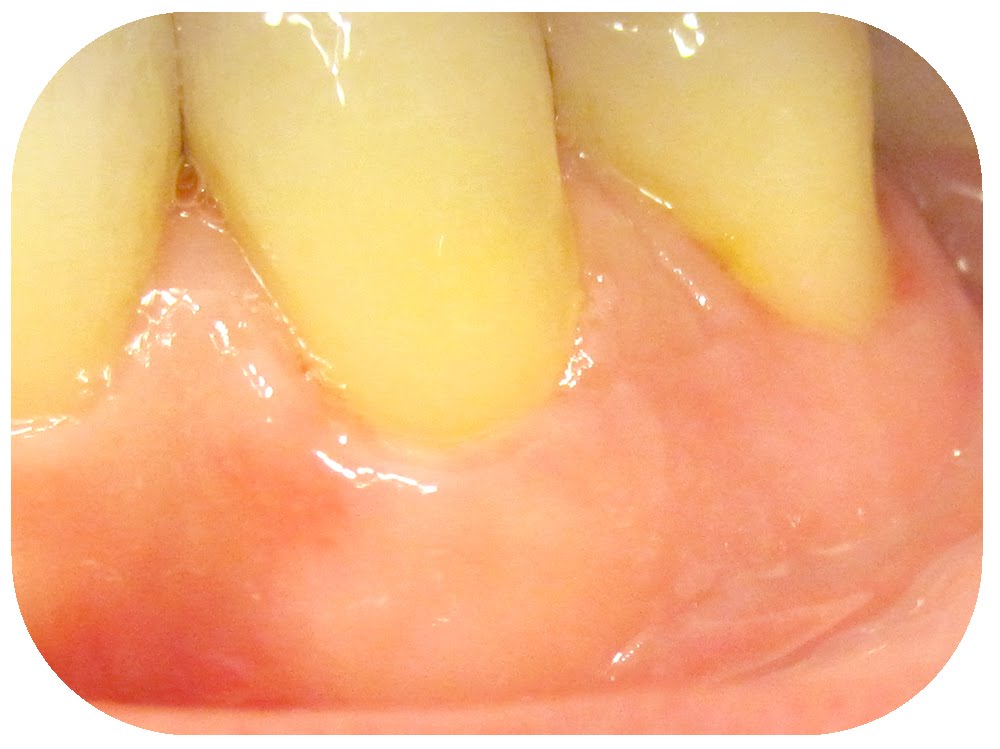

Gum Graft Experience Reddit . A gum graft might refer to a few different procedures, but all of them involve putting new gum tissue in a part of your mouth where your current gum tissue is receding. Read 30 reviews of gum graft to see what real people have to say about their experience, including cost, recovery time & if it. I had gum grafting surgery three weeks ago on seven teeth. I just had my gum graft 5 days ago on one lower front tooth and as another person mentioned, it’s really not so bad! I did my typical deep dive. Worth noting, i underwent the pinhole produce, which is a bit different from a. Gum graft surgery is a dental procedure for treating thinning gums or gum recession. Gum grafting is a standard procedure that helps restore receding gums, protect teeth, and improve smiles. If you’re considering this procedure or. Gum grafting covers exposed teeth. If anyone out there has doomscrolled on here worrying and panicking about gum graft surgery, not everyone has a horrible, traumatic.